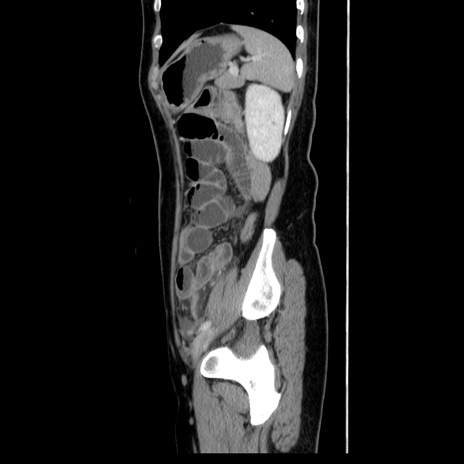

症例39(矢状断像)

【症例】40歳代女性

【主訴】上下腹部痛

【現病歴】2日目から下腹部痛あり。夜間は痛みで眠れなかった。昨日より上腹部痛と下痢が出現。臥位で痛みは軽快したため、休んでいた。本日になって臥位でも立位でも痛みが強くなってきたため救急要請。

【既往歴】子宮内膜症

【身体所見】部:平坦・軟、左上下腹部に圧痛あり、反跳痛あり。

【データ】WBC 21800、CRP 26.78

CT